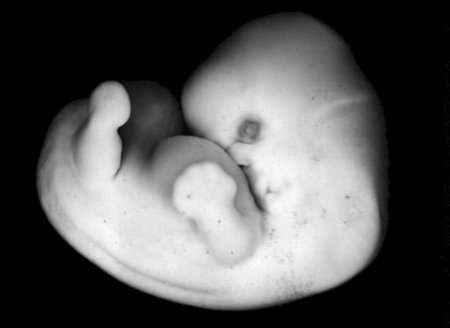

Развитие плода на 7-й неделе беременности характеризуется формированием всех жизненно важных органов, волосяных фолликул, век, языка. Растёт туловище, локти и пальчики приобретают более отчетливые очертания. Почти полностью сформировались кишечник, печень, лёгкие, почки.

На этой неделе определяются зачатки глаз, живот и грудь, а на ручках проявляются пальцы. У малыша уже появился орган чувств — вестибулярный аппарат.

Длина эмбриона — до 12 мм. У плода уже определяется лицо, можно даже различить его ротик, носик и ушные раковины. Головка у зародыша крупная и ее длина на этой неделе уже соотносится с длиной туловища. На этом этапе развития тельце плода уже почти полностью сформировалось.